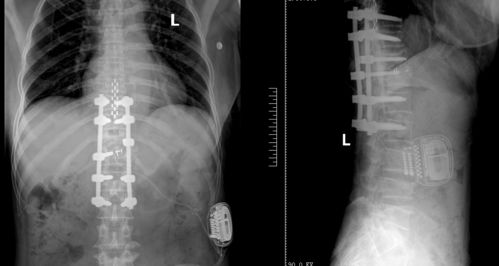

甘肃省第二人民医院疼痛科成功实施首例脊髓电刺激植入术

曲径市二院脊髓电刺激疗法成功开展缓解神经性疼痛在曲径市二院,一项创新的脊髓电刺激技术成功开展,为一名长期受神经性疼痛困扰的患者带来了显著的缓解。这项技术的实施,标志着该院在神经调控治疗领域迈出了重要的一步,为众多神经性疼痛患者带来了新的希望。脊髓电刺激器,一种精密的医疗设备,通过植入患者脊髓附近,释放微弱的电流,以干扰疼痛信号的传递,从而达到减轻或消除疼痛的效果。这种治疗方法特别适用于那些对传统药物治疗反应不佳的患者。在一名女性患者的案例中,脊髓电刺激疗法显示出了其卓越的效果。在接受了脊髓电刺激治疗后,患者的疼痛感明显减轻,生活质量得到了极大的提升。这一成功案例不仅为患者带来了实质性的帮助,…